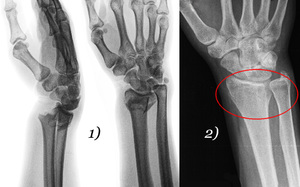

Врачи отмечают, что перелом лучевой кости со смещением является одной из наиболее распространенных травм, особенно среди людей, занимающихся спортом или подвергающихся риску падений. Специалисты подчеркивают важность своевременной диагностики и адекватного лечения, так как неправильное сращение кости может привести к долгосрочным осложнениям, включая ограничение подвижности и хроническую боль. Врачи рекомендуют проводить рентгенографию для точного определения характера перелома и его смещения. В большинстве случаев требуется хирургическое вмешательство для восстановления правильного положения кости. После операции необходима реабилитация, включающая физиотерапию, что способствует быстрому восстановлению функции руки. Важно, чтобы пациенты следовали рекомендациям врачей и не игнорировали симптомы, чтобы избежать серьезных последствий.

- Рентгенография: Основным методом диагностики является рентгенография, которая позволяет визуализировать перелом и определить его тип, а также наличие смещения костных фрагментов.

- Компьютерная томография (КТ): В некоторых случаях, особенно при сложных переломах, может потребоваться КТ для более детального изучения повреждений.